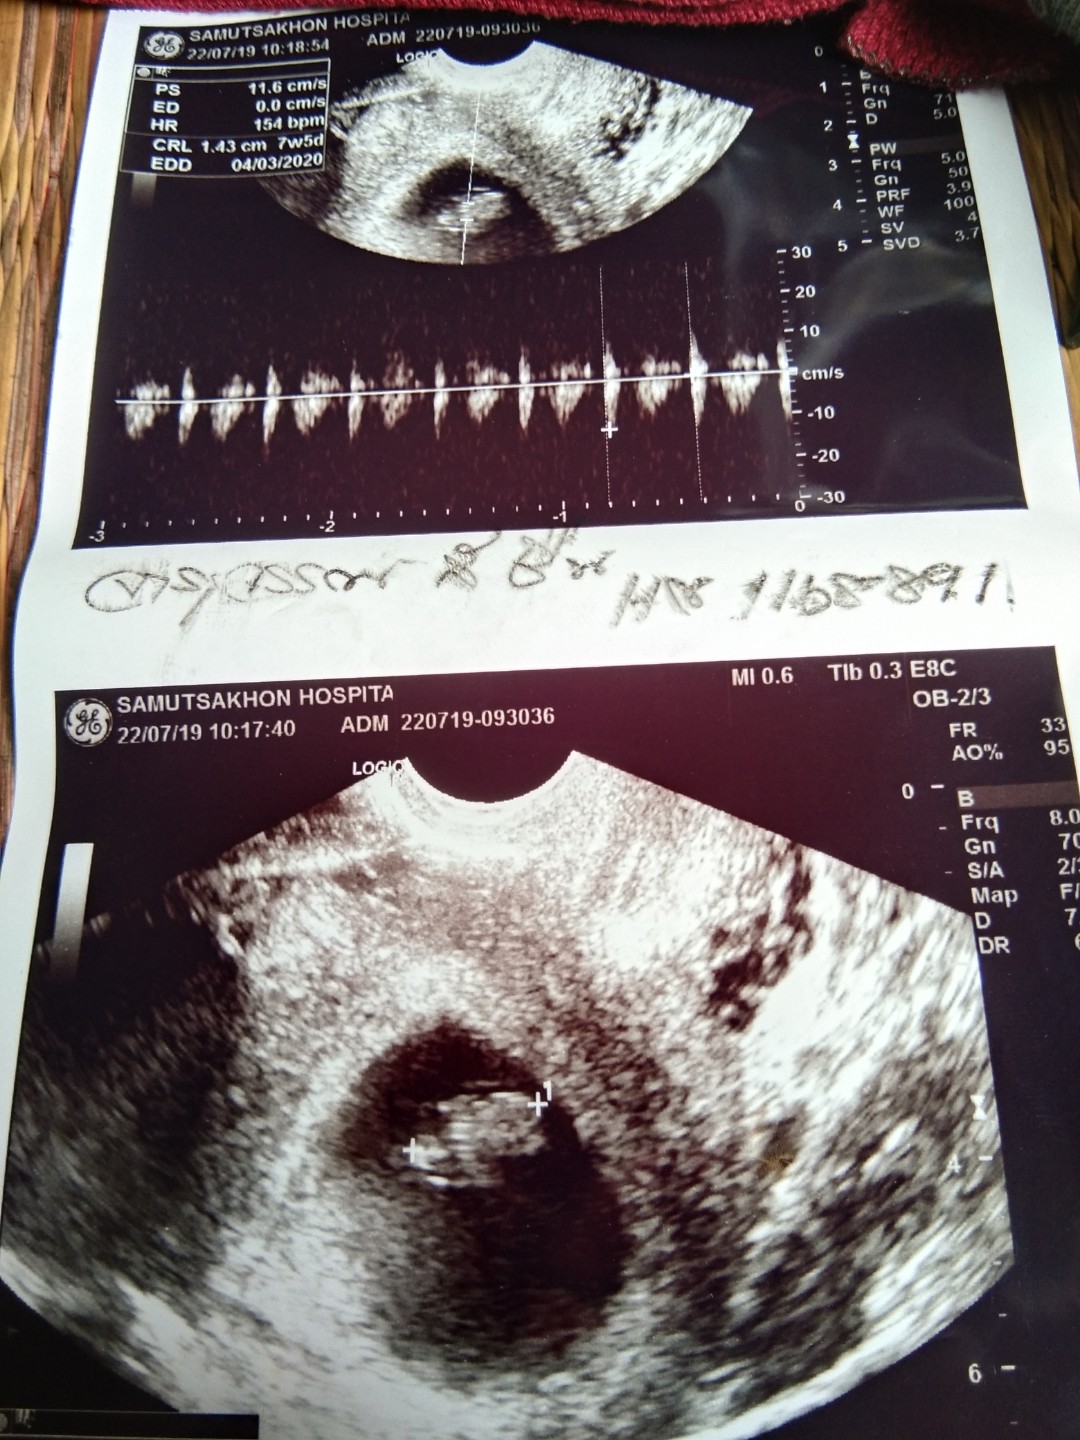

7สัปดาห์จ้า

ภาพแรก7week 6day.